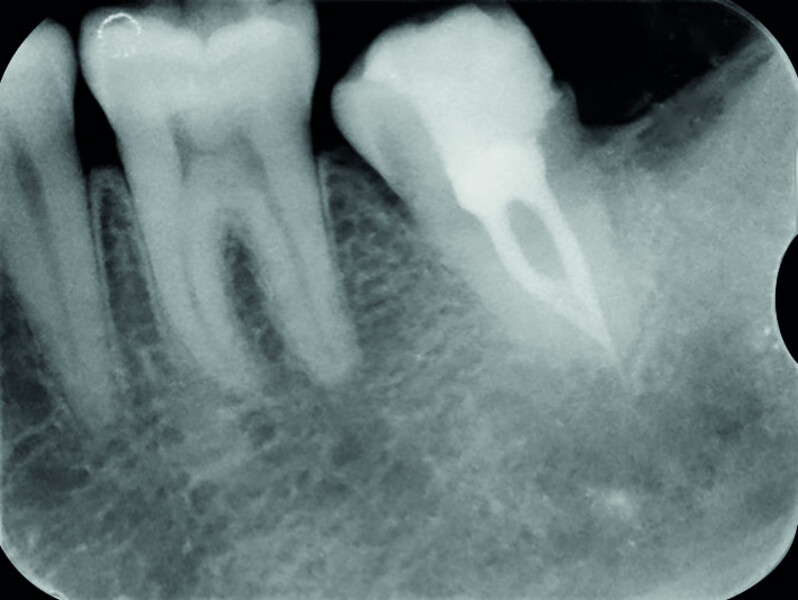

Fig. 19a: Radiographs: Pre-op periapical.

Fig. 19b: Radiographs: Immediately after transplantation.

Fig. 19c: Radiographs: One-year recall.

Fig. 19d: Radiographs: Two-year recall.